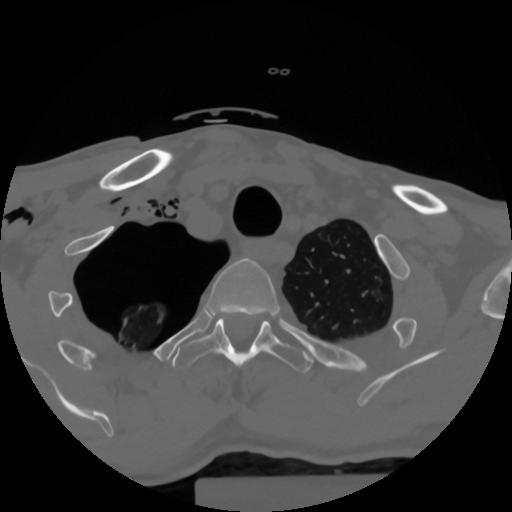

12 P.BLANDAS,,Vol,0.5,P.BLANDAS,,